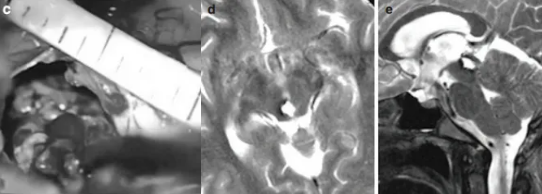

于是沒過不久,巴教授再次為喜喜主刀手術。巴教授選擇經(jīng)幕下小腦上入路暴露病變,術中發(fā)現(xiàn)病變?yōu)榈湫偷暮>d狀血管瘤,而且還出現(xiàn)了新鮮的病灶內出血,很難想象如果沒有及時手術,喜喜又將面臨怎樣的危急時刻。